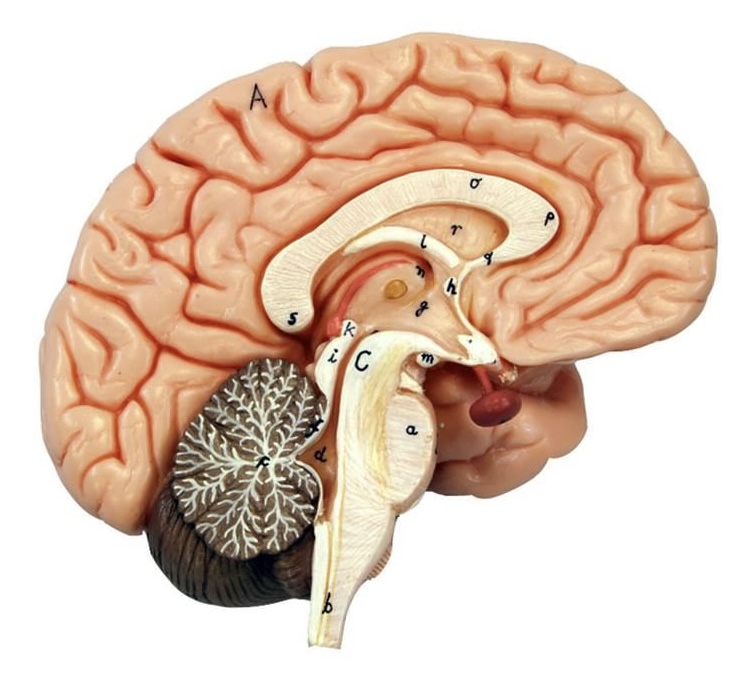

What is D?

lateral ventricle

Imagine thin membrane separating the 2 lateral ventricles

septum pellucidum

What is C?

3rd ventricle

What is B?

cerebral aqueduct

What is A?

4th ventricle

What is below A at the very end?

central canal (spinal cord)

What is C?

midbrain

tectum (corpora quadrigemina): superior colliculus

tectum (corpora quadrigemina): inferior colliculus

What is a?

pons

medulla oblongata

intermediate mass of thalamus

hypothalamus

What is the pink bulb?

pineal gland

corpus callosum

fornix

What is A?

cerebral cortex

cerebral tracts

cerebral hemispheres

longitudinal fissure

What are these ridges?

gyri

What are these shallow grooves?

sulci

Divides parietal from frontal lobe

central sulcus

precentral gyrus

postcentral gyrus